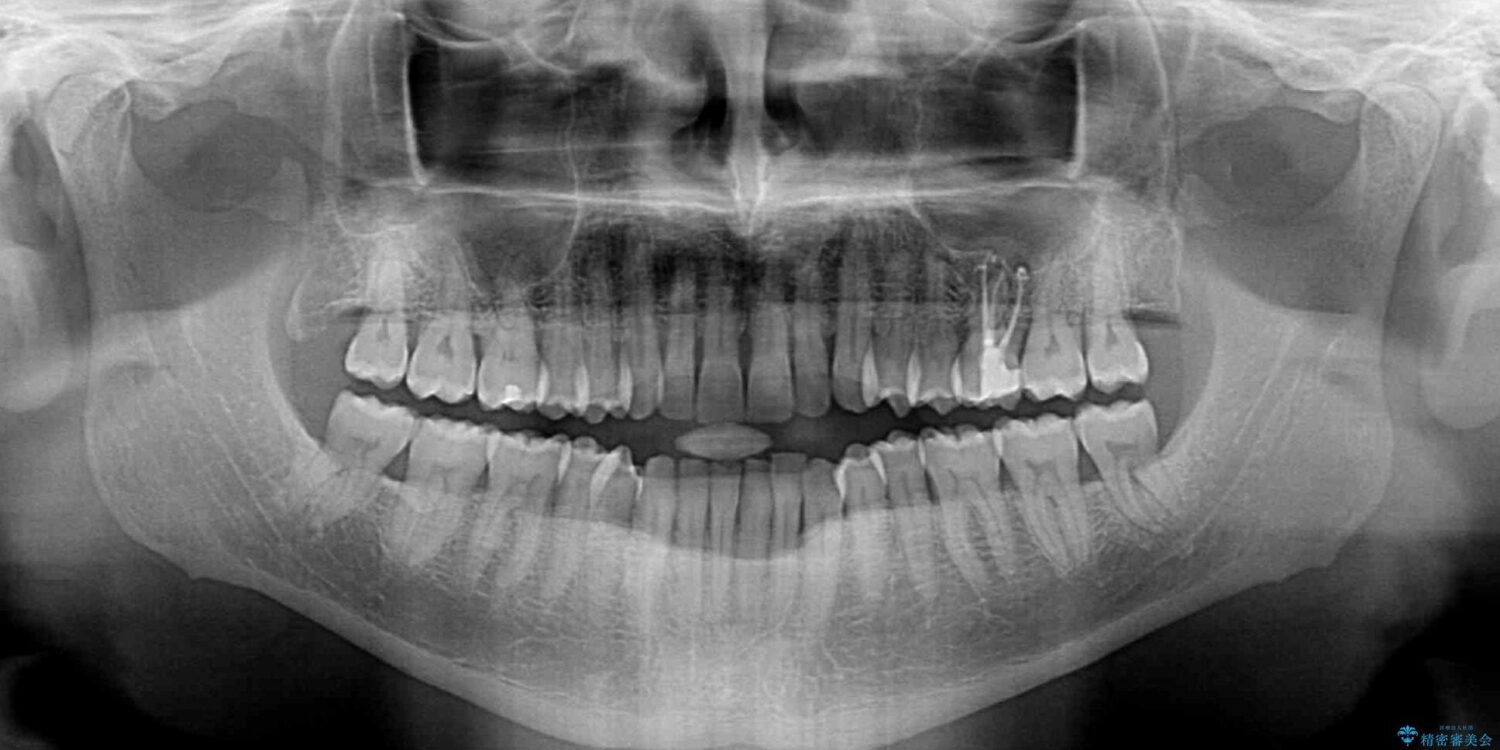

前歯でものを噛みきりたいとのことで来院された患者様です。

治療計画

以前矯正治療を経験されたそうですが、舌の突出癖により上下前歯に隙間ができている様子でした。

前歯の非接触改善は、インビザラインの得意とするところですが、マウスピース矯正は絶対に継続できないとのことで、ワイヤー装置にて矯正治療を行うこととしました。

舌の突出癖が改善されない限り、非接触改善は見込めないため、トレーニングを徹底するように指示しました。

治療前

• 前歯でものを噛みきりたい 目立たない装置でのワイヤー矯正 治療前画像